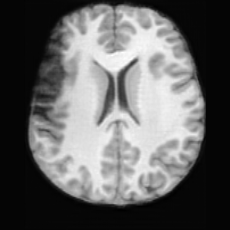

Pathology-to-Healthy Editing. Fig. 5 (a) presents comparison results on four input brain images with lesions of varying sizes, shapes, and densities. All competing models, although specialized for healthy brain image synthesis, struggle to reconstruct pathological regions, especially near lesion boundaries. In contrast, USB accurately reconstructs the corresponding healthy brain, even in challenging cases with large, high-density lesions where normal brain structures are almost completely obscured (last row). Tab. 2 provides a quantitative comparison for pathology-to-healthy editing, where USB achieves the best performance across all three datasets, demonstrating the effectiveness of its unified framework in reconstructing healthy brains from pathological inputs. Additional results are in Suppl. B.

Healthy-to-Pathology Editing. As shown in Fig. 5 (b), given a healthy brain image paired with a random lesion mask, USB seamlessly embeds the lesion into the healthy anatomy, producing realistic pathological appearances consistent with surrounding structural context. Yet UNA’s syntheses are visually unrealistic, with the conditioned lesion mask simply overlaid as a parallel layer onto the healthy brain. Tab. 3 further demonstrates USB’s superior performance. The evaluation was conducted on 100 pairs of lesion masks and healthy brains, with real stroke images